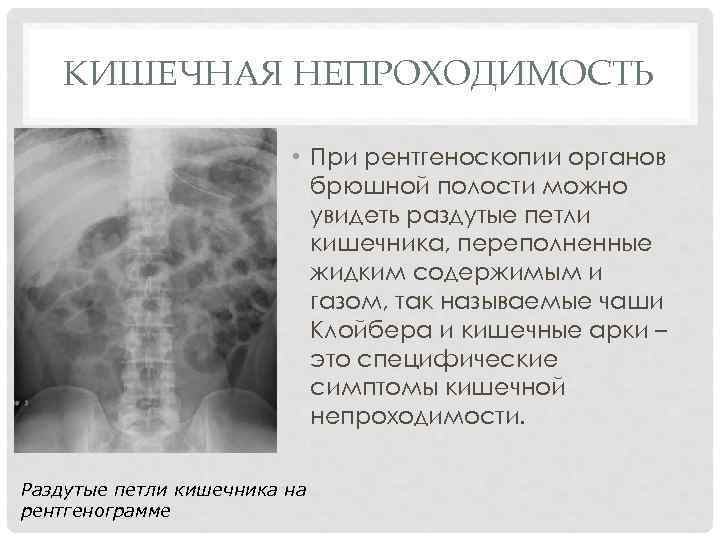

Иллюстрации и информация о симптомах острого кишечного непроходимости